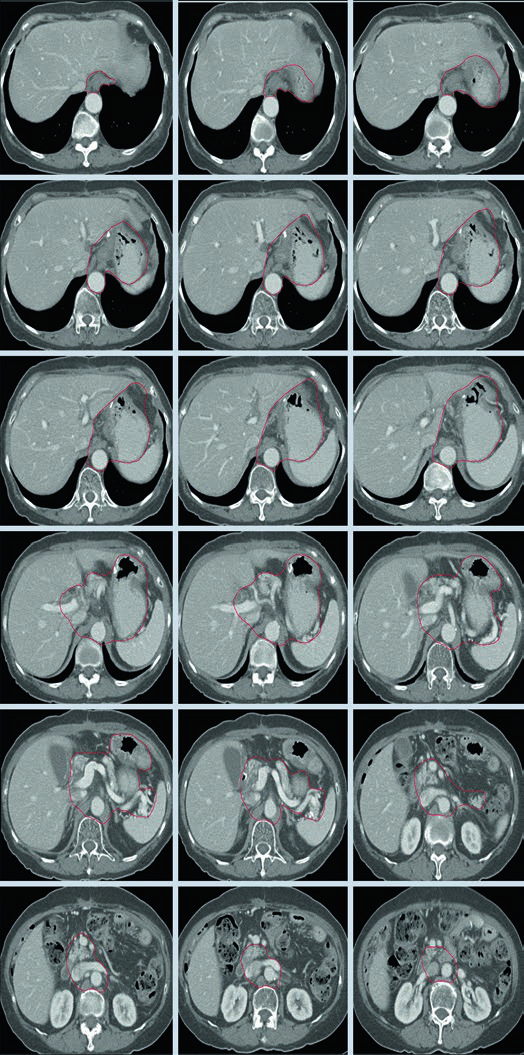

Caso 3: T2N1M0 Adenocarcinoma de Antro/Piloro — Gastrectomia Distal

No adenocarcinoma de antro/piloro, o CTV abrange a anastomose gastrojejunal, o estômago remanescente, o ligamento hepatogástrico e o coto duodenal. A cobertura do hilo esplênico é opcional neste cenário. A inclusão do coto duodenal é preferencial em gastrectomias parciais por tumores distais/antrais, mas não deve ser incluída em pacientes com tumores proximais submetidos a gastrectomia total.